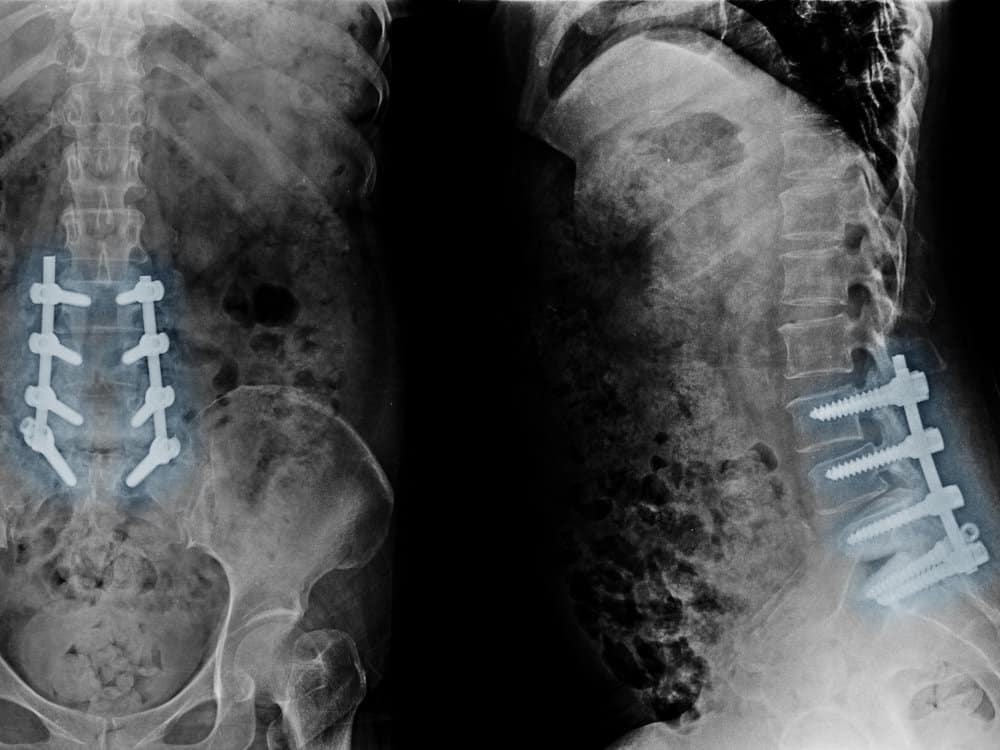

Bei Rückenleiden wird in Deutschland zu schnell zum Messer gegriffen – das stellte der Sachverständigenrat des Bundesministeriums für Gesundheit schon vor über 20 Jahren fest. Eine Analyse der Bertelsmann-Stiftung zeigt nun, dass sich daran in der Zwischenzeit nicht viel geändert hat und welche Gründe es dafür gibt.

Rückenschmerzen sind eine Volkskrankheit, etwa 85 Prozent der Bevölkerung leiden mindestens einmal in ihrem Leben darunter.1) In seinem Gutachten für das Gesundheitsministerium hob der Sachverständigenrat hervor, dass konservative Therapien in vielen Fällen wirkungsvolle Behandlungsmöglichkeiten bieten, Rückenprobleme dauerhaft in den Griff zu bekommen. Demzufolge waren viele Operationen unnötig, die schonenden Behandlungsmöglichkeiten wurden nicht ausreichend ausgeschöpft.2)

Eine Analyse der aktuellen Situation in der Gesundheitsversorgung zeigt, dass diese Fehlversorgung zwei Jahrzehnte später nach wie vor besteht. Zu diesem Schluss kommt eine Studie der Bertelsmann-Stiftung. In ihrem „Faktencheck Rücken“ analysierte die gemeinnützige Organisation unter anderem die Entwicklung operativer Eingriffe in Deutschland über einen Zeitraum von etwa 15 Jahren.3) Der aktuelle Bericht des Sachverständigenrates bestätigt diese Ergebnisse eindrücklich.4)